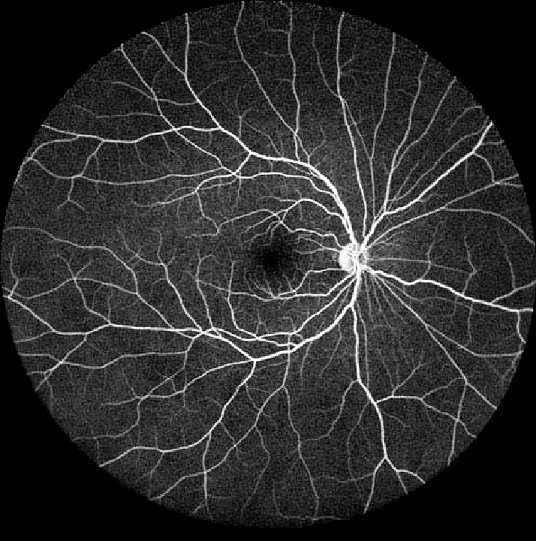

Furthermore, generated images from FA images are presented in Fig. 6 and Fig. 7. Results in the images are nearly identical to the original images, because original networks are applied to stylize color images. However, six generated images contain more concise features than the original ones, which helps ophthalmologists make better judgments. Therefore, this style transferring networks can fulfill edge sharpening and enhancement of contrast. No matter which kinds of images are generated, advanced features in new disease images still exist. Furthermore, analyses of image performance by EyeNet and CAMs for prediction are presented in a later section.

Figure 6: Three FA fundus images with symptom of drusen and corresponding generated images. (a), (b), (c) Original images. (d), (e), (f) Generated images.

Figure 7: Three FA fundus images with symptom of GA and corresponding generated images. (a), (b), (c) Original images. (d), (e), (f) Generated images.